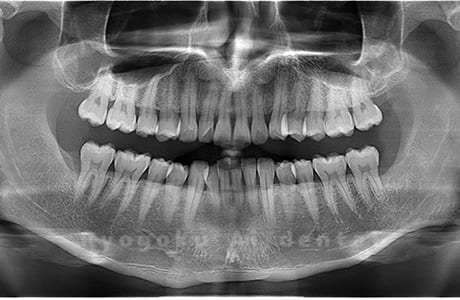

Case03

- 原因

- 上顎、下顎の親知らず

- 治療内容

- 上下4本の親知らずを抜歯したケースです。

<リスク・副作用>

手術後は痛み、腫れ、痺れなどの副作用が生じる場合があります。